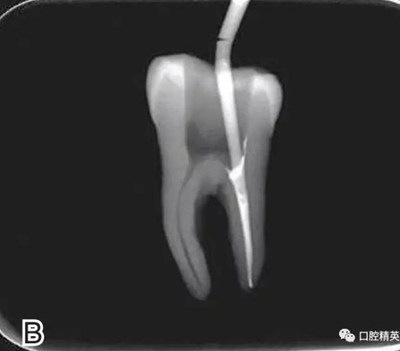

要求工作尖能自由到達(dá)距根尖4~5 mm(有學(xué)者提出3~4 mm)的位置并能輕微接觸根管壁,用橡皮片做好標(biāo)記(圖1)。

圖1 選擇攜熱器工作尖,A.試攜熱器尖 B.工作尖在根內(nèi)的位置